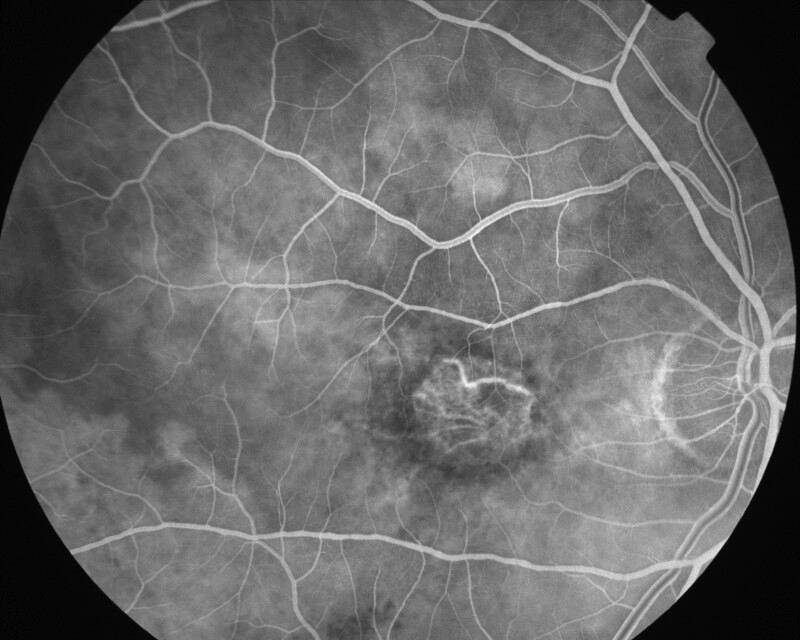

ATROPHIE AREOLAIRE CENTRALE

IMG0001.JPG